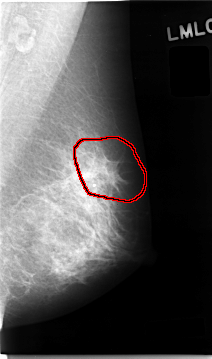

C_0026_1.LEFT_MLO

LEFT_MLO LINES 4656 PIXELS_PER_LINE 2752 BITS_PER_PIXEL 12 RESOLUTION 50 OVERLAY

FILE: C_0026_1.LEFT_MLO.OVERLAY

TOTAL_ABNORMALITIES 1

ABNORMALITY 1

LESION_TYPE CALCIFICATION TYPE AMORPHOUS DISTRIBUTION CLUSTERED

LESION_TYPE MASS SHAPE ARCHITECTURAL_DISTORTION MARGINS SPICULATED

ASSESSMENT 4

SUBTLETY 2

PATHOLOGY MALIGNANT

TOTAL_OUTLINES 1

BOUNDARY